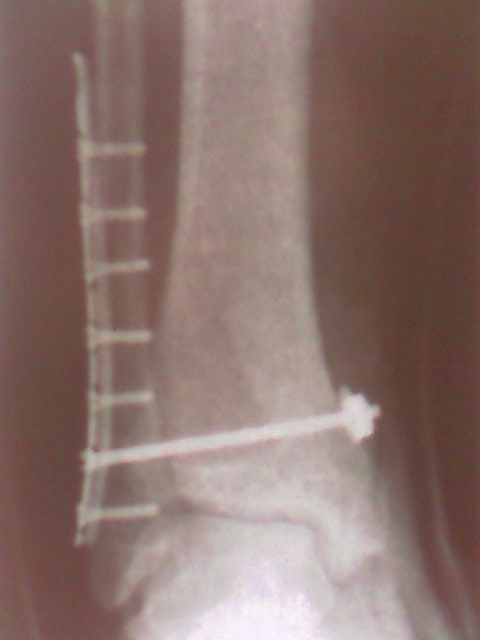

И мне недавно поставили. Точно такую же штуку как на рентгене у автора.. И нога так же левая, и даже средний болт так же торчит с другой стороны=)

Вот только на второй кости еще два шурупа. Очень хочется уже поскорее начать нормально ходить. Ну что ж, всем "киборгам" скорейшего выздоровления=)

У меня тоже стоит. Но ничего про снятие не говорили. Мешает зараза. Стопа не до конца сгибается.

Насколько я поняла, ее ставят временно, на год.. Чтобы кости срослись правильно и ничего не мешало в будущем подвижности стопы.. Плюс, дополнительная жесткость при нагрузке.. А потом, пластина уже не нужна.. У меня подвижность стопы полностью восстановлена, спасибо врачам и физиотерапевтам

Стальная.. Ее ставили на год, изначально планируя в итоге снять.. Дядя-доктор объяснил, что в мне не стоит оставлять в организме металл.. Да и потом, она немного выпирала.. Я ее пальцами могла прощупать.. Брррр